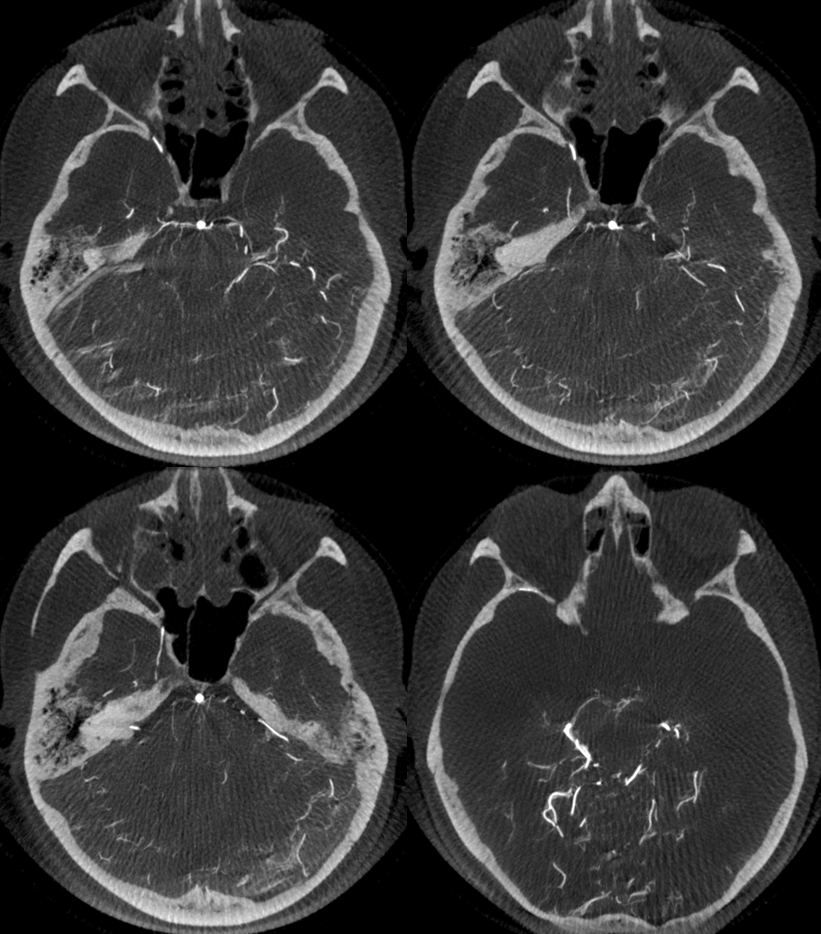

Angio shows large trigeminal with clear supply of the SCA on lateral view. Vert injection shows no right SCA. There is a diminuitive branch from mid-basilar projecting laterally — that is likely the right labyrinthine artery — what is embryologically solid AICA territory. The rest is taken by the trigeminal. The right PICA is limited to vermian territory. The inferolateral hemisphere is supplied by the trigeminal as well. Dont look for arrows. You should figure it out.

MIP images. Superior vermian territory = white oval; lateral SCA territory = dashed white oval; AICA (minus the labyrinthine branch) = dashed black oval; inferior PICA/down to tonsillar branch = black oval

And, in case you really dont believe its the trigeminal artery, check out these co-registration images of angio (axial MIP reconstructions of rotational angio) and finally with superimposed tractography of the Vth nerve! Images courtesy Dr. Nader Delavari

Superimposed MRI and angio axials (our trigeminal artery is shown bi arrow)

Now with tractography of CN V